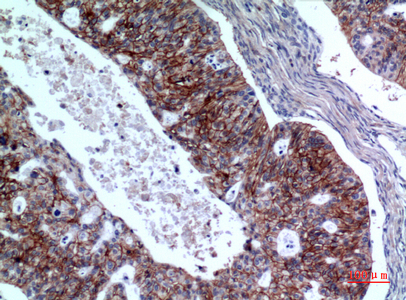

![IL1 Receptor 2 antibody [N3C3] detects IL1 Receptor 2 protein at cytoplasm in human colon cancer by immunohistochemical analysis. Sample: Paraffin-embedded human colon cancer. IL1 Receptor 2 antibody [N3C3] (GTX108702) diluted at 1:500.

Antigen Retrieval: Citrate buffer, pH 6.0, 15 min](https://www.genetex.com/upload/website/prouct_img/normal/GTX108702/GTX108702_40016_20150420_IHC_2_w_23060120_741.webp)